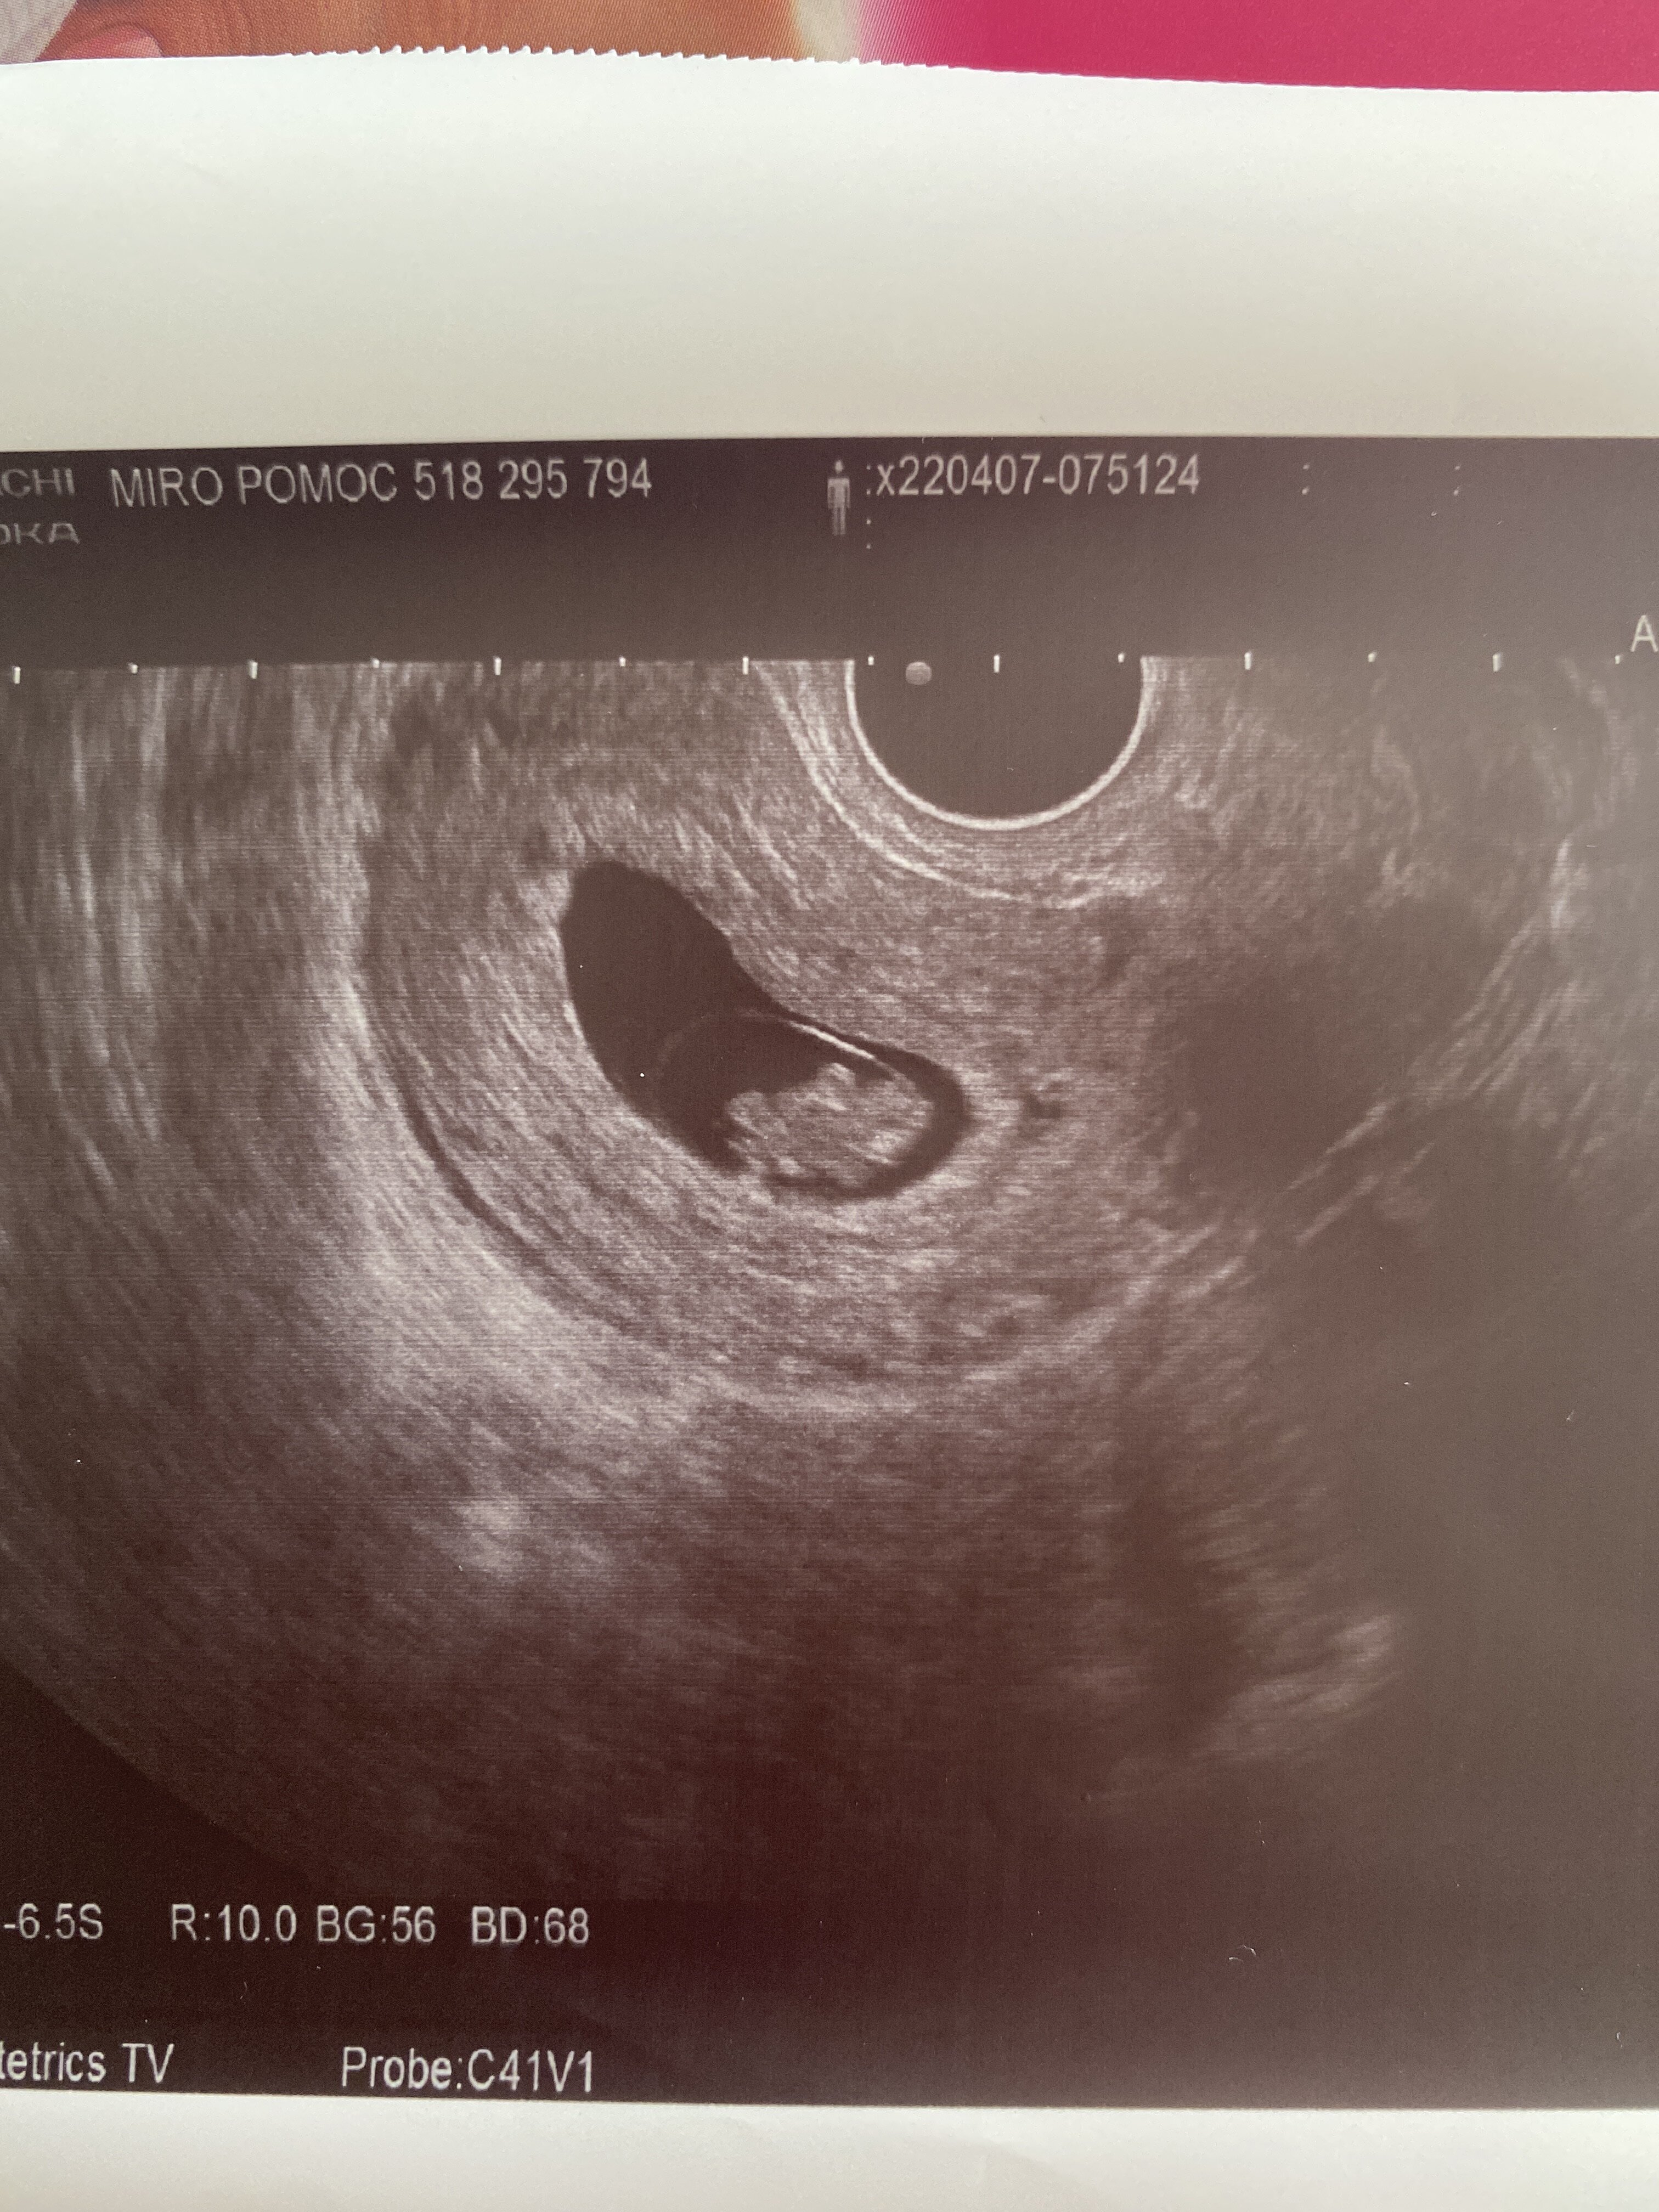

Jestem już po wizycie, póki co wszystko w porządku. Bąbel ma 1,82cm, serduszko szybko mu bije, mózg jest, płyny mózgowo rdzeniowe w porządku. Za dwa tygodnie kolejna wizyta i wtedy założymy kartę ciąży, lekarz mówi że zakłada jak ma 100% pewności że się dobrze rozwija, a ja poroniłam ostatnio w tych okolicach 8 tygodnia więc zaczekamy. Niby się cieszę ale dalej się boje 🙈 babie nie dogodzisz 🤣

Termin z USG zrównał się z tym z miesiączki, więc to chyba dobrze, bobo nadgonilo 😁 Zobacz załącznik 1387504

To ja tez się pochwałę moim maluchem 💚

Albo sobie coś wmawiam, albo widzę tam już mini rączki i nóżki 😍